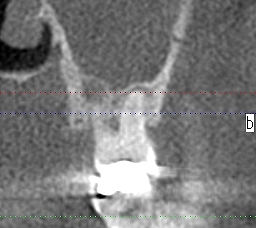

術前のCTになります

根尖病巣が認められます

少しずつずらしていきます

根尖病巣が上顎洞にはじけているのが確認できます

炎症が上顎洞に波及しているのがわかりました